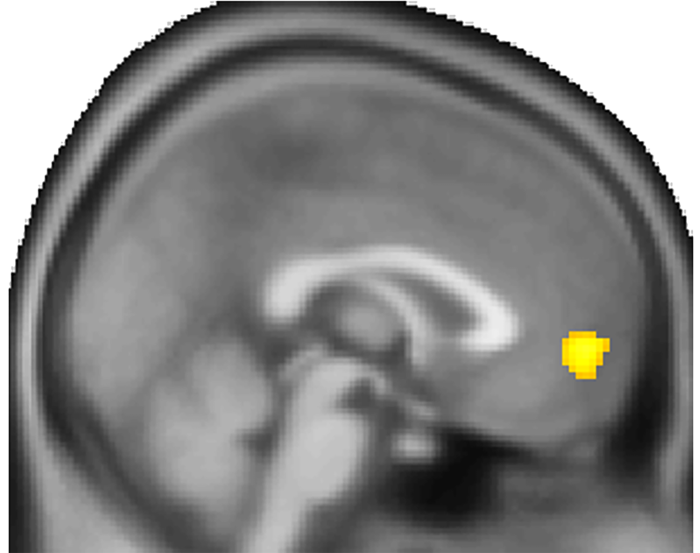

Finally, the results of the brain scans suggested that these choices were being driven by neural activity in the ventromedial prefrontal cortex, a decision-making center known to be involved in forward thinking. For instance, the two-step forward thinking computer simulation helped explain the changes in this area of the brain better than other simulations or when applied to other brain regions.

“These results expand the role of both the ventromedial prefrontal cortex and of forward thinking in our lives,” said Dr. Gu. “In the future, we plan to explore how problems in the brain’s forward thinking app may play role in depression, schizophrenia and other neuropsychiatric disorders.”